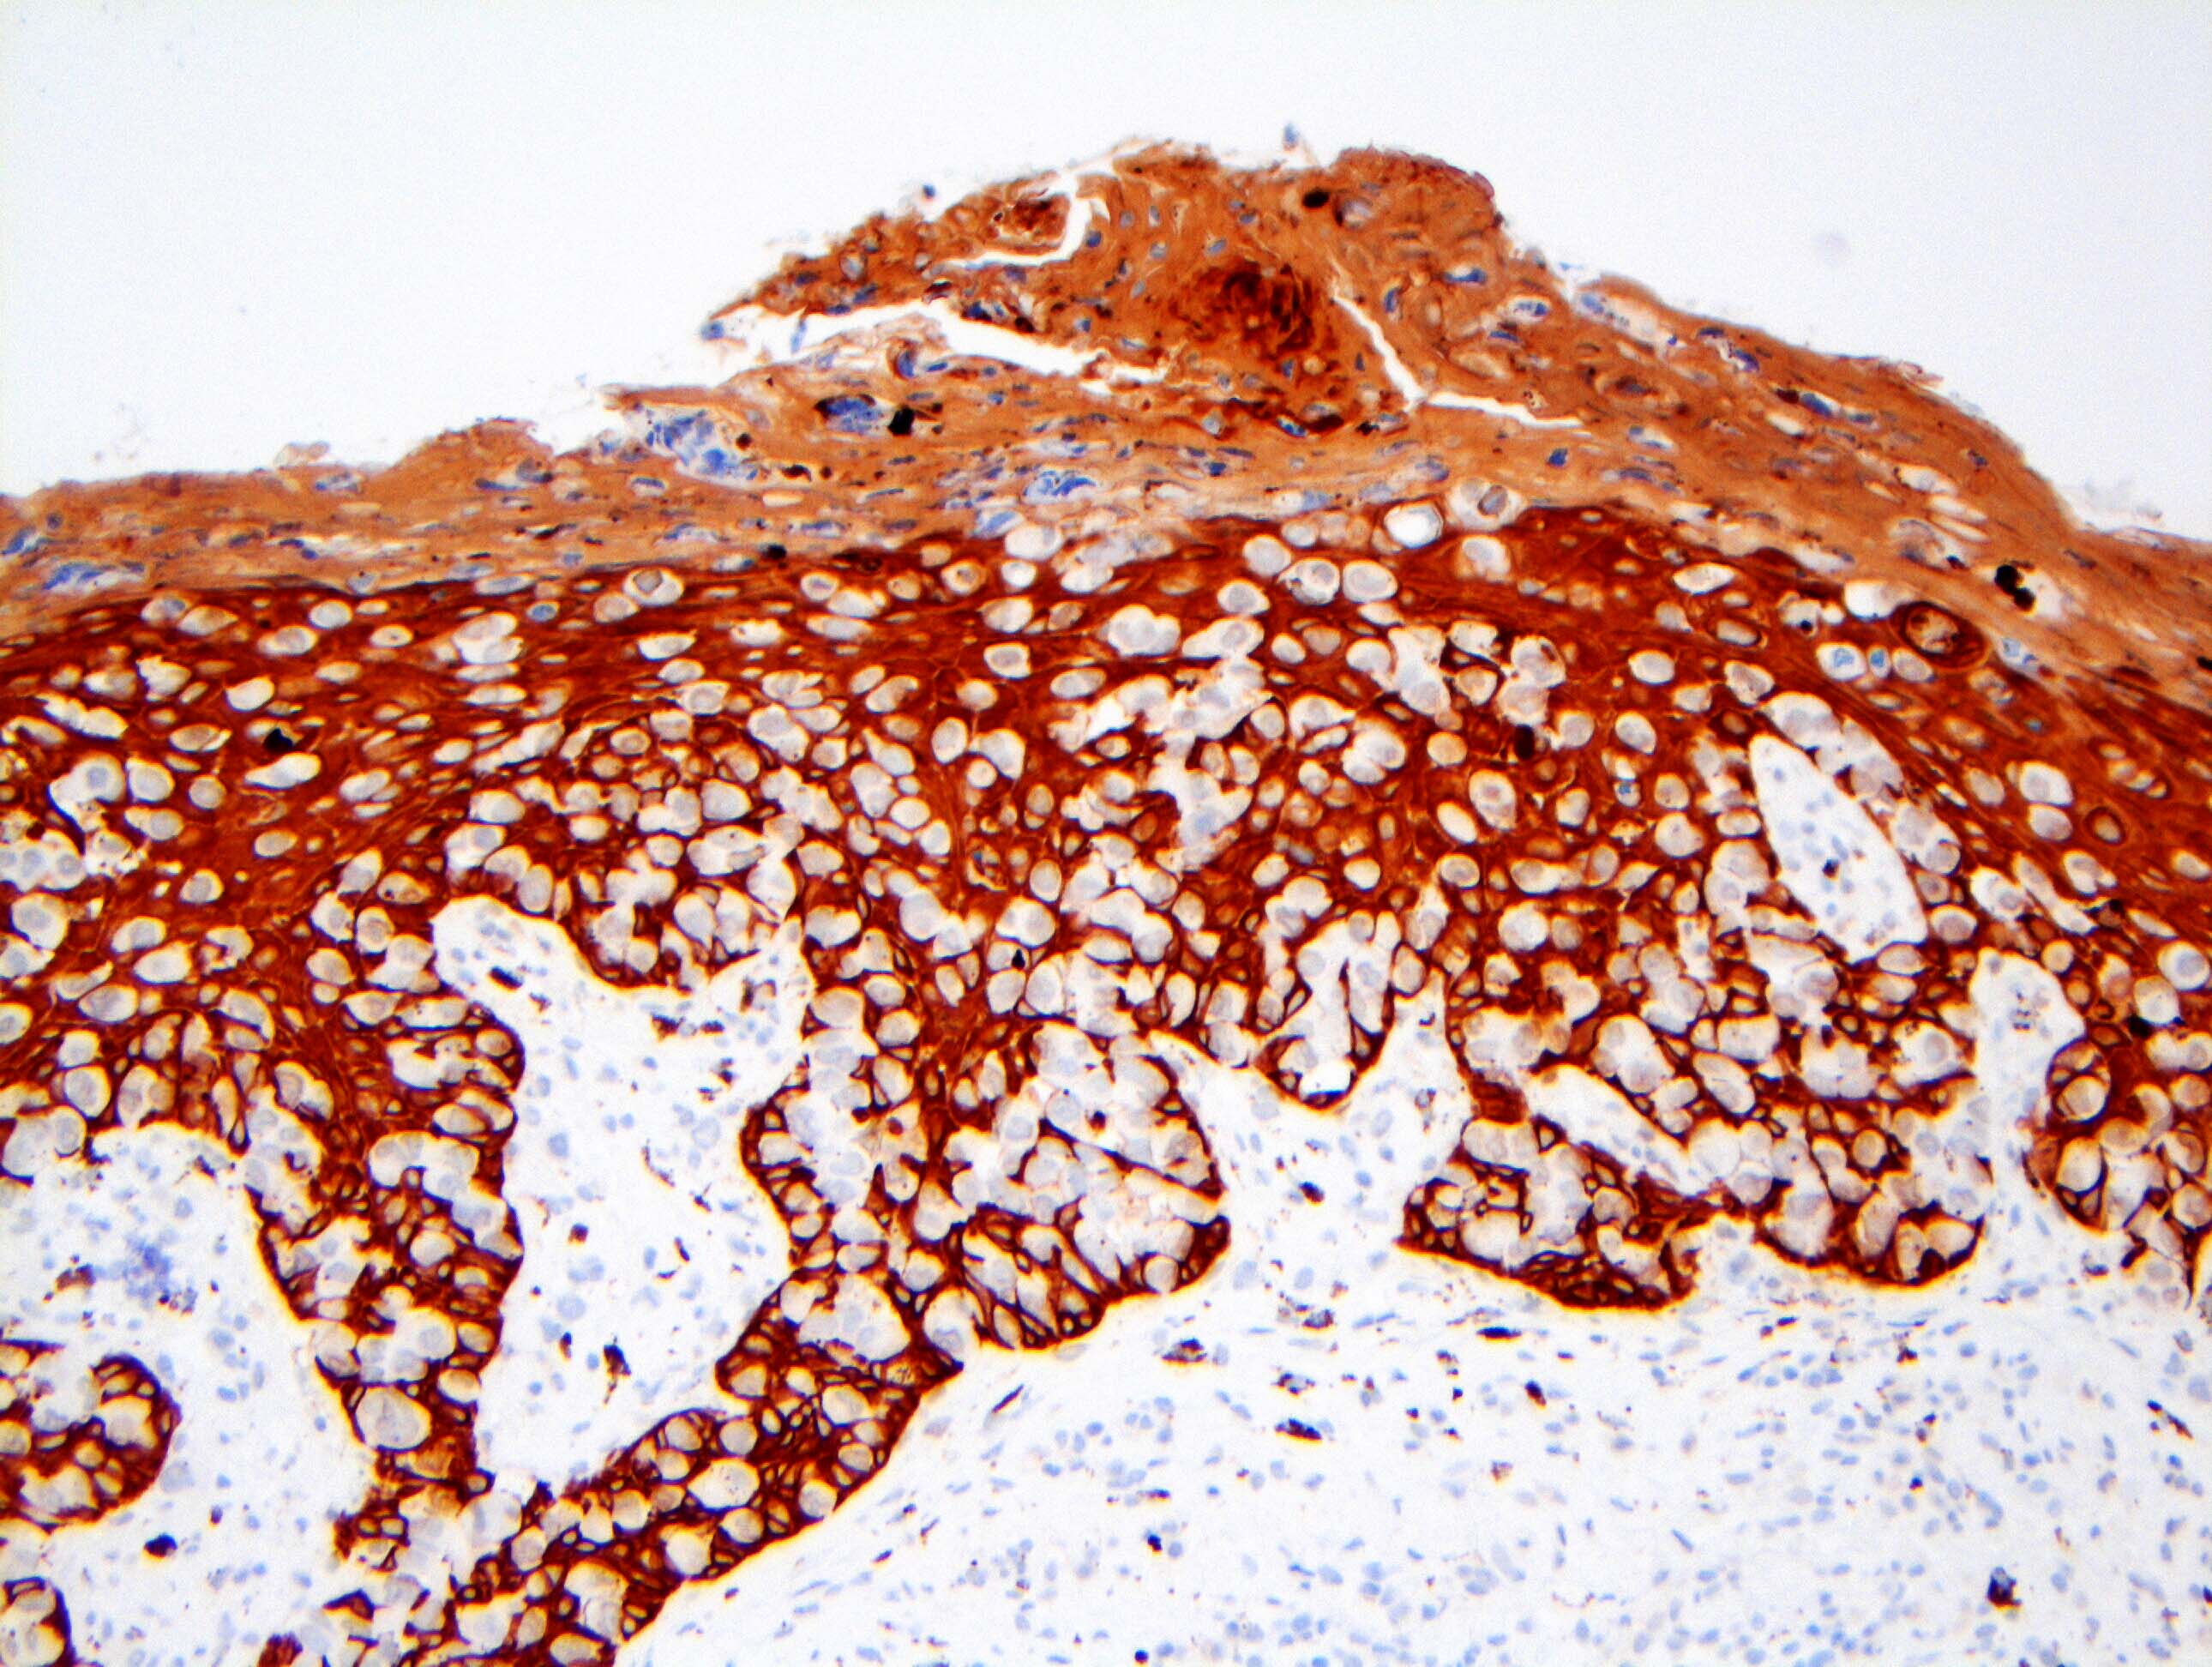

Microscopic (histologic) images

Contributed by Anna Biernacka, M.D., Ph.D. and Mary Ann Gimenez Sanders, M.D, Ph.D.

Positive stains

- CK7 (> 90%)

- HER2 (80 - 100%)

- CAM5.2 (70 - 100%)

- ER (10 - 40%)

- PR (0 - 30%) (Breast Cancer Res Treat 2013;141:1)

- Comment: The tumor cells are positive for CK7 and HER2 (3+) by immunohistochemistry, supporting the above diagnosis of Paget disease. ER and PR show no staining of in situ nuclei.